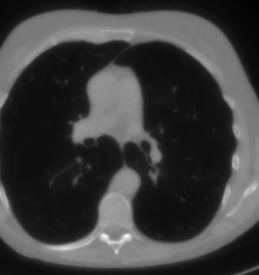

The considered images are pixel reconstructions of human abdomen, computed from full-dose acquisitions. In Figure 2 we depict one image with two zooms-in highlighting areas with different anatomical structures, such as pulmonary details, sections of ribs and low-contrast inter-costal muscles.

In all the experiments reported in 5.1, we have used the images from the data set as ground truth references.

Coherently, we simulate the tomographic projections of the ground truth images, according to a 2D fan-beam geometry, and we add to the sinograms white Gaussian noise with noise level.

To address sparse-view CT reconstructions, we considered two different protocols: the first one is a full angular acquisition with 1-degree spaced projections (we call it in the following); in the second one the scanning trajectory covers degrees and computed only projections (it is labelled as ).